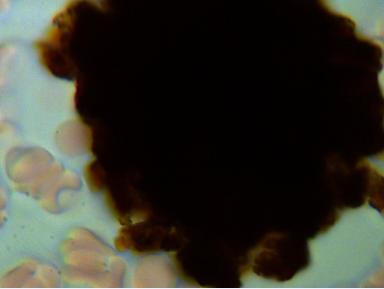

1.CHOLESTEROL

Podczas badania często stwierdzana jest obecność kryształków cholesterolu. W zależności od ich wielkości możemy określić zagrożenie rozwoju miażdżycy, wystąpienia zawału czy zakrzepu. Nawet jeżeli wartości biochemiczne mieszczą się w normie to przede wszystkim wielkość a w mniejszym stopniu ilość blach cholesterolowych zwiększa ryzyko wystąpienia choroby.

Powiększenie 1600x - aby wykonać zdjęcie całej blachy trzeba było wykonać cztery zdjęcia.